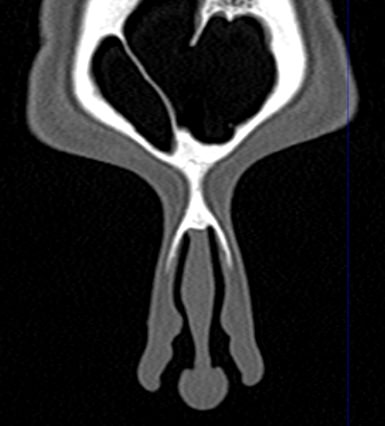

В современной отоларингологии широко применяется мультиспиральная компьютерная томография для диагностики различных заболеваний ЛОР-органов. КТ относится к лучевым методам исследования, который с помощью рентгеновских лучей позволяет получить детальное изображение костных структур, хрящей носа, околоносовых воздухоносных пазух и прилегающих областей.

Воспалительные заболевания, такие как гайморит или синусит верхнечелюстных пазух, этмоидит, сфеноидит и фронтит достоверно визуализируются при помощи компьютерной томографии. Полученные данные помогают врачу специалисту в верификации диагноза и утверждении эффективного плана лечения. На фоне воспалительных изменений нередко встречаются полипозные образования, а при запущенных случаях синуситов очень важно подтвердить или исключить наличие участков деструкции костных перегородок.

Аппараты сканируют область исследования в течение нескольких секунд, производя одномоментно от 64 до 128 тончайших срезов толщиной от 0,5 мм. Высокая скорость сканирования обеспечивает минимальную дозу облучения для пациента. При этом получаются четкие изображения с высоким контрастным разрешением, что дает возможность рассмотреть исследуемую зону в мельчайших подробностях. Кроме того, томографы создают объемные 3D-изображения области носа и прилегающих пазух, что помогает в оценке пространственного соотношения анатомических структур, выявленной патологии и способствует проведению точной диагностики.